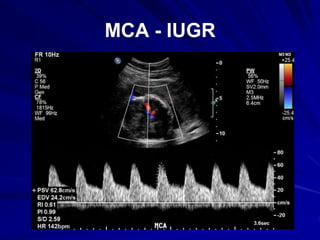

MCA - IUGR

Doppler wave form of early stage of fetal

hypoxaemia

• Increased end-diastolic flow (EDF) in the

middle cerebral artery

– ↓MCA pulsatility index (PI) / resistance index (RI)

• Decreased end-diastolic flow in the umbilical

artery

– ↑umbilical artery RI